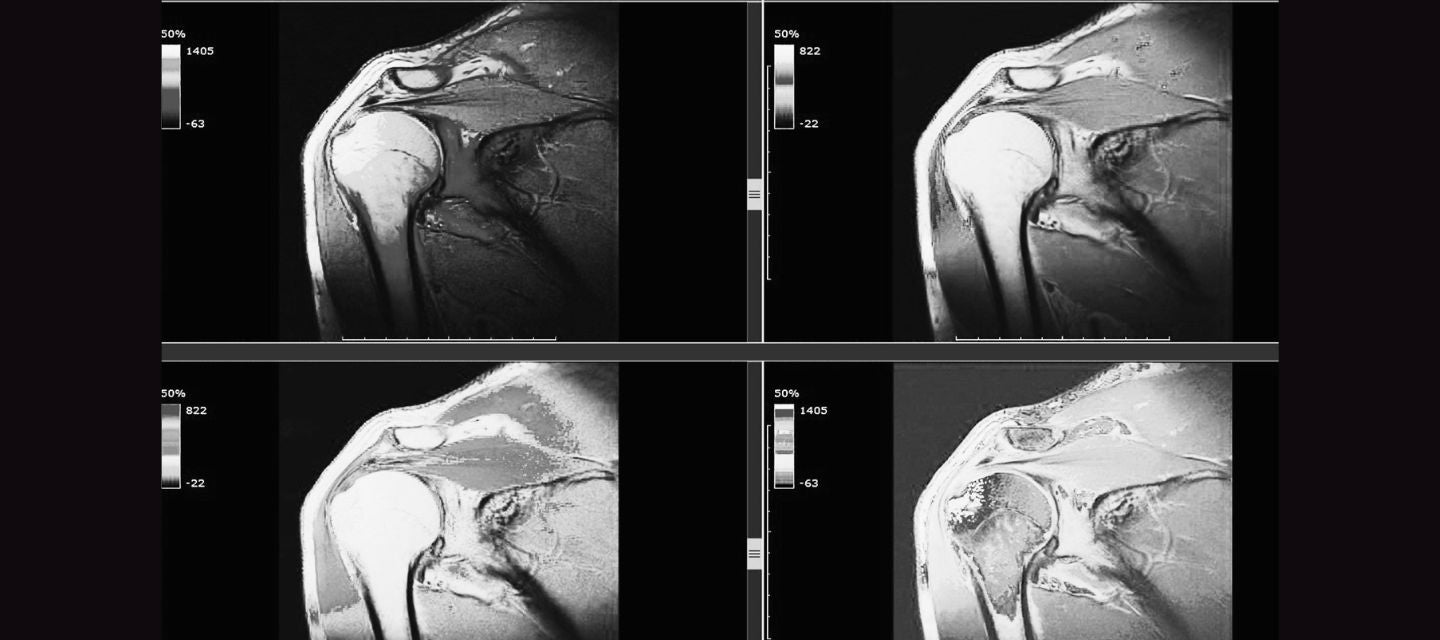

MRI Shoulder Musculoskeletal Imaging How Is A Shoulder Mri Done Magnetic resonance imaging (mri) of the shoulder is done to: Magnetic resonance imaging (mri) of the shoulder is an advanced medical imaging technique that plays an important role in diagnosing shoulder. Magnetic resonance imaging (mri) of the shoulder uses a powerful magnetic field, radio waves and a computer to produce detailed pictures of the. Find problems in the shoulder, such. How Is A Shoulder Mri Done.

MRI Shoulder Musculoskeletal Imaging How Is A Shoulder Mri Done Magnetic resonance imaging (mri) of the shoulder is an advanced medical imaging technique that plays an important role in diagnosing shoulder. A shoulder mri uses radio waves, a magnet and a computer to produce images of the shoulder. Magnetic resonance imaging (mri) of the shoulder uses a powerful magnetic field, radio waves and a computer to produce detailed pictures of. How Is A Shoulder Mri Done.

MRI Shoulder Musculoskeletal Imaging How Is A Shoulder Mri Done Mri scans are considered as the most comprehensive diagnostic tool available for the. Find problems in the shoulder, such as arthritis, bone. A shoulder mri uses radio waves, a magnet and a computer to produce images of the shoulder. What is a shoulder mri? Magnetic resonance imaging (mri) of the shoulder is done to: While an mri scan can be. How Is A Shoulder Mri Done.